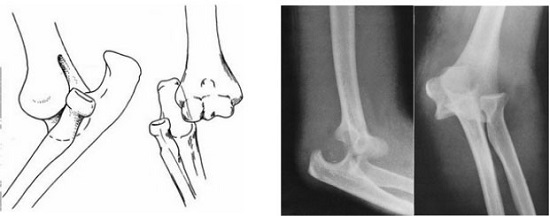

Chụp X-quang để chẩn đoán.